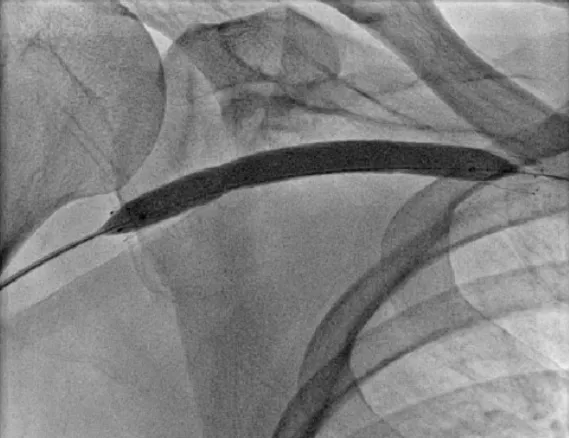

Intoxicação por citrato na contínua: quando suspeitar e como tratar